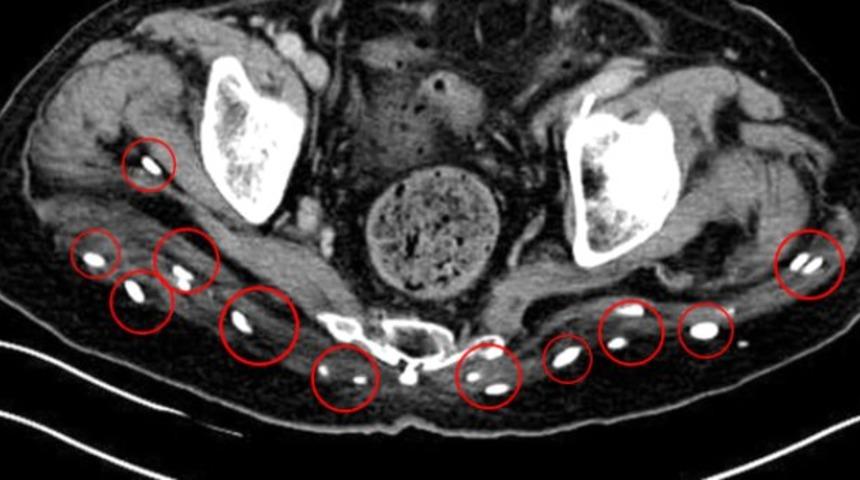

Doktorlar, yapılan tetkikler sonucu adamın vücudunun neredeyse her yerinde yüzlerce minik solucan yumurtası olduğunu görünce dehşete düştüler.

Filmler, yumurtaların beyninde, omurgasında, kalçalarında, boynunda, göğsünde ve bacaklarında olduğunu gösteriyor.